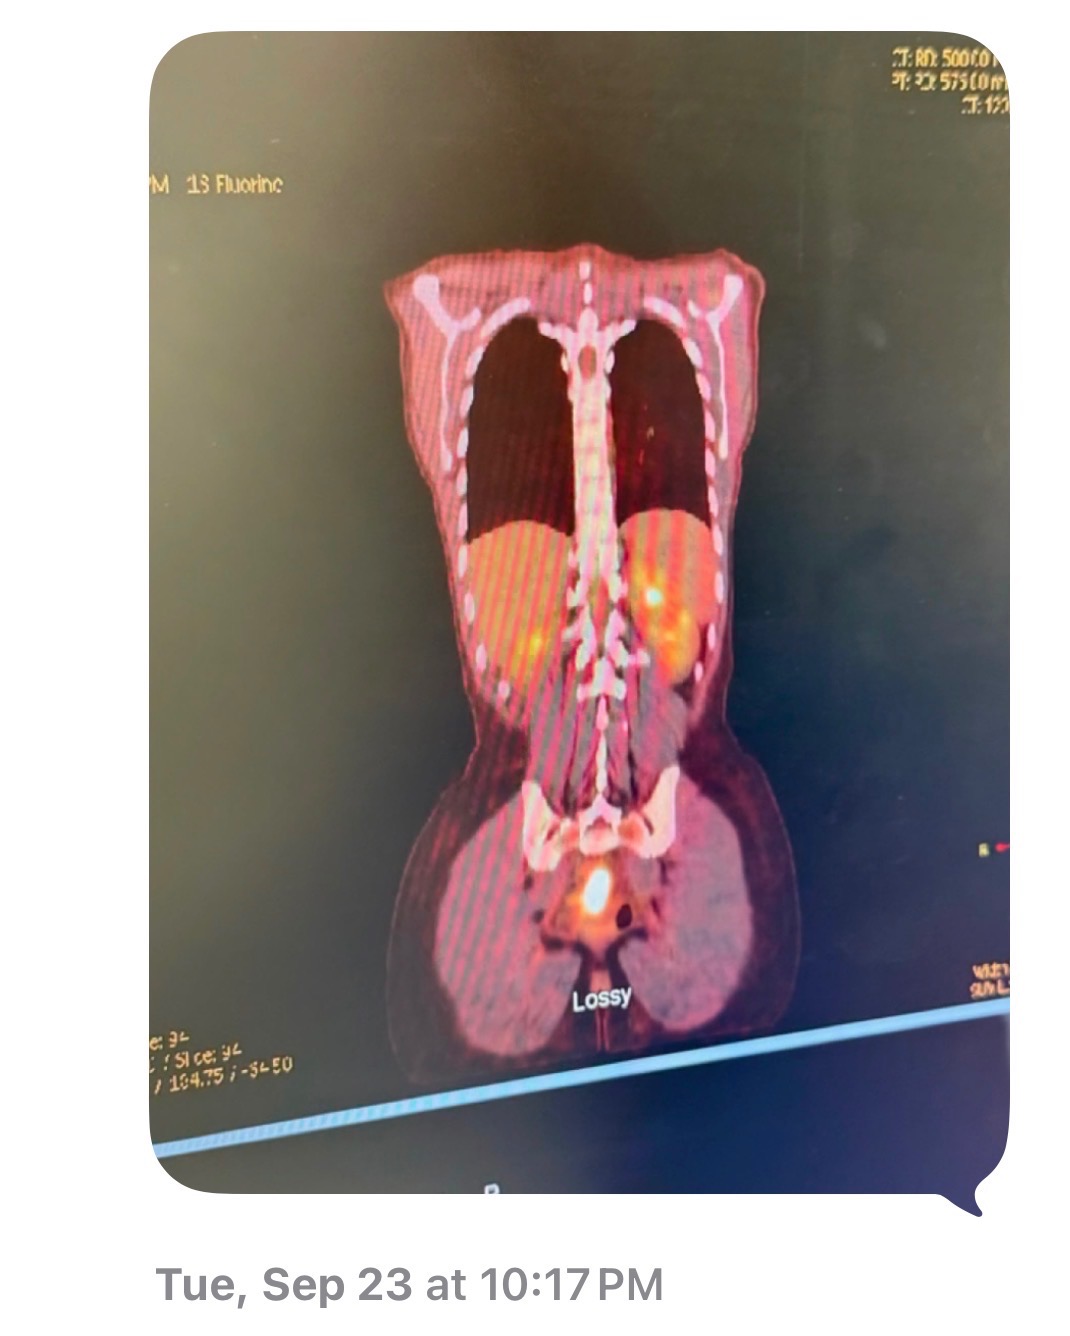

Description: Aspen Gomez, my daughter, was diagnosed with stage four rectal cancer in July. She has already undergone treatment and surgery to remove the mass, but despite her strength and determination, the cancer has spread to her lungs and outside her stomach. Now, she needs more treatment to have a fighting chance. Unfortunately, MD Anderson will not accept her insurance for the immunotherapy they offer, and we are trying to raise money to have it done by April 19. This is the only chance we have to help Aspen get the care she needs.